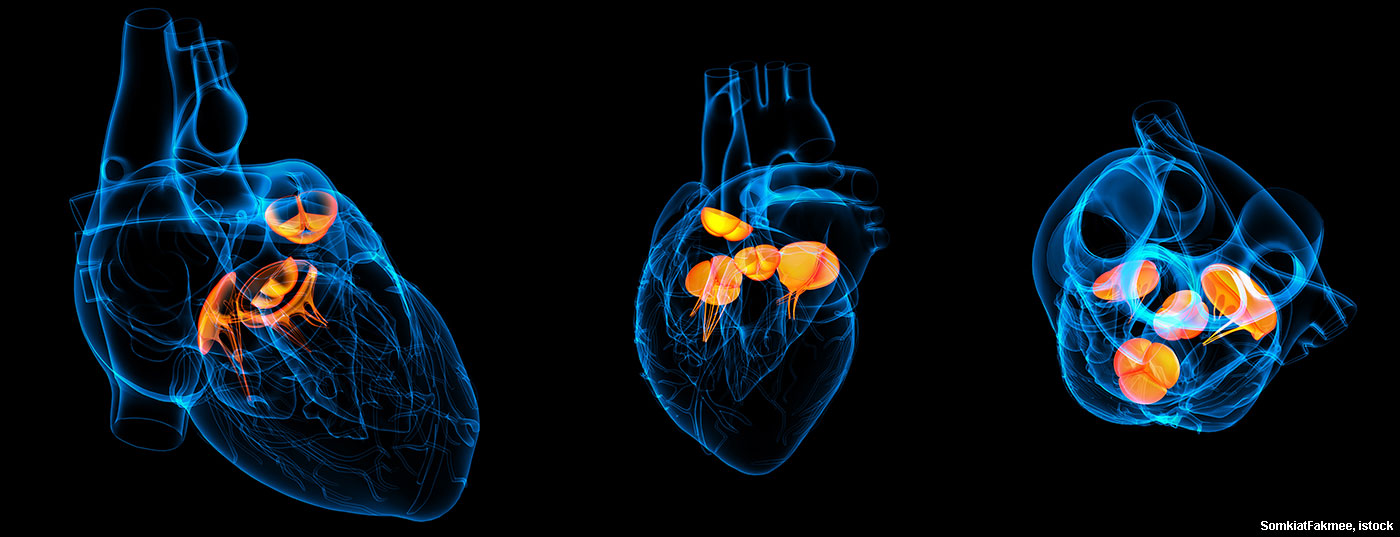

Der medizinische Fortschritt hat auch Auswirkungen auf die Epidemiologie der infektiösen Endokarditis. Gerade Katheterklappenimplantationen (TAVI) werden zukünftig eine grosse Herausforderung darstellen.